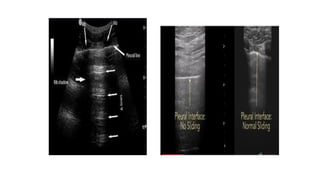

PNEUMOTHORAX

• Identification of a lung point on lung US yields 100% specificity

for pneumothorax

• normal pattern is called the seashore sign as it depicts the

boundary between the stationary chest wall (“ocean”) and

moving lung (“sand”)

• When a pneumothorax is examined at M-mode US, the smooth

horizontal lines are uninterrupted, as the chest wall and air

deep to the pleura are both stationary in pneumothorax

• This appearance of pneumothorax at M-mode examination has

been dubbed the bar code sign

• SEASHORE SIGN-NORMAL LUNG • BARCODE SIGN -

PNEUMOTHORAX • Identification ofa lung point on lung US yields 100% specificity for pneumothorax • normal pattern is called the seashore sign as it depicts the boundary between the stationary chest wall (“ocean”) and moving lung (“sand”) • When a pneumothorax is examined at M-mode US, the smooth horizontal lines are uninterrupted, as the chest wall and air deep to the pleura are both stationary in pneumothorax • This appearance of pneumothorax at M-mode examination has been dubbed the bar code sign

• SEASHORE SIGN-NORMALLUNG • BARCODE SIGN - PNEUMOTHORAX